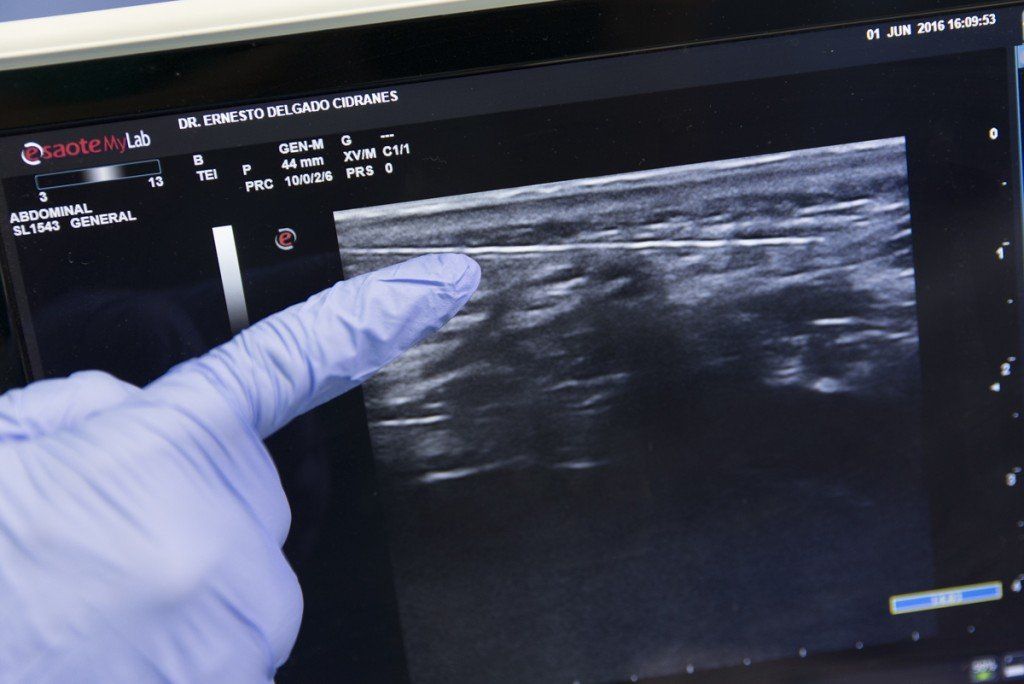

ECOGRAFÍAS (urológicas y ginecológicas)